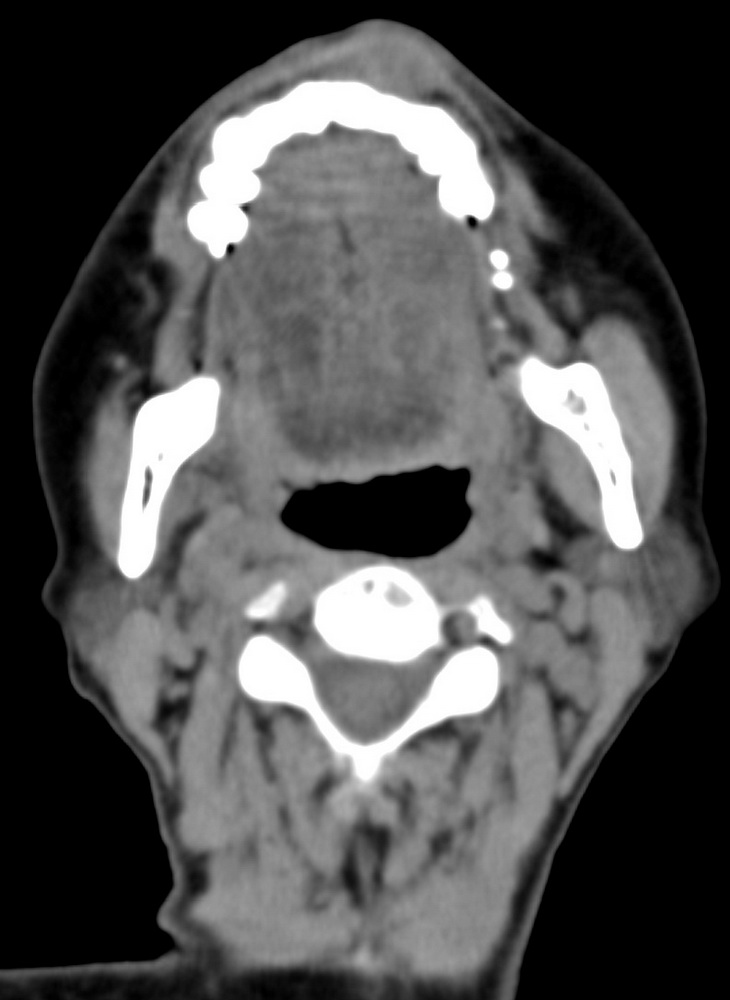

女,68岁。发现上唇无痛性肿块2年多,查体局部皮肤隆起,其余未见异常。

病灶ct值约42hu。

病理结果:唾液腺混合瘤。